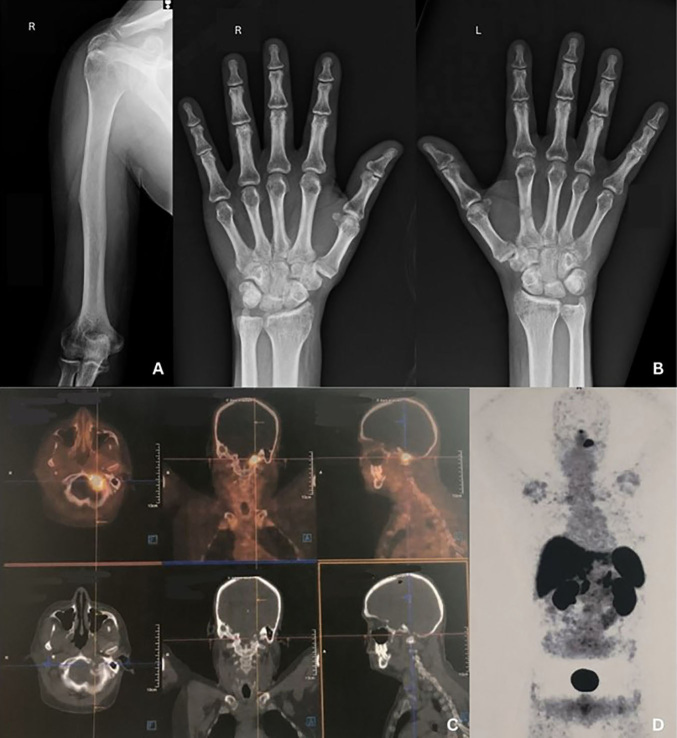

An image of a FGF-23-producing tumor resulting in osteomalacia.

产生 FGF-23 的肿瘤导致骨软化症的图像。